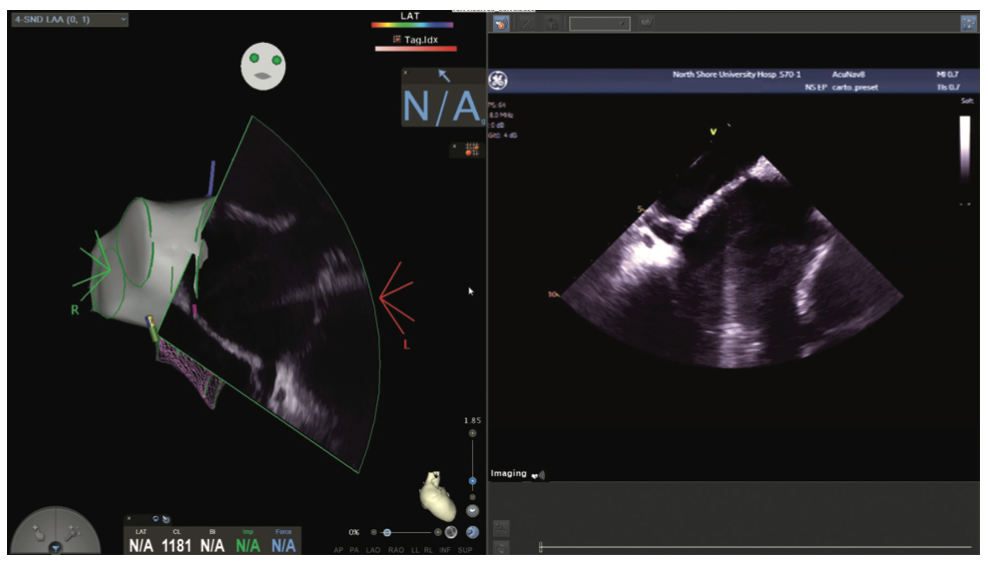

Figures/Videos 1-10 demonstrate the process of navigation from groin access to the heart to create biatrial geometry, localize the esophagus, and gain transseptal access. Many currently practicing electrophysiologists use very little fluoroscopy to map and ablate the left atrium (LA) with the current multielectrode catheters and EAM systems once transseptal access is obtained.

The videos and figures included here should be beneficial in helping to reduce or eliminate fluoroscopy during complex ablations. It is important to note that there is a learning curve and one should not hesitate to use fluoroscopy to safely and effectively perform procedures based on the operator’s comfort. Despite the sophisticated mapping and ablation tools currently available, one should not base ablation strategy primarily on color maps, but rather on a thorough understanding of the electrograms, sampling windows, and conduction properties from which they are derived. The additional use of ICE for anatomic confirmation further enhances efficacy and safety.